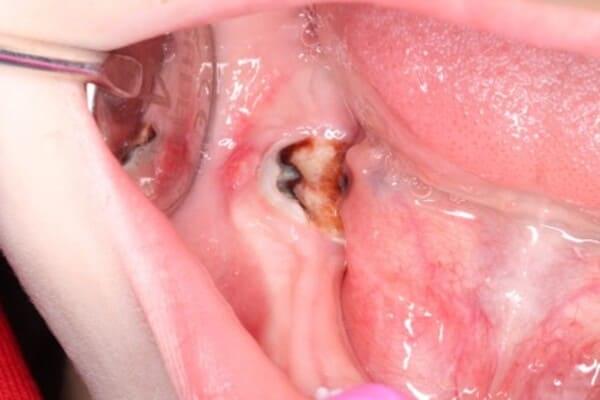

Проблема виникає, коли нерв (пульпа) постійного зуба передчасно гине від травми чи інфекції. Це критично, адже саме пульпа відповідає за ріст кореня. Без неї корінь залишається коротким і тонким. Такий зуб не може витримувати жувальне навантаження і ризикує бути втраченим. Це як дерево з великою кроною та маленьким корінцем: найменший вітер може його вирвати.